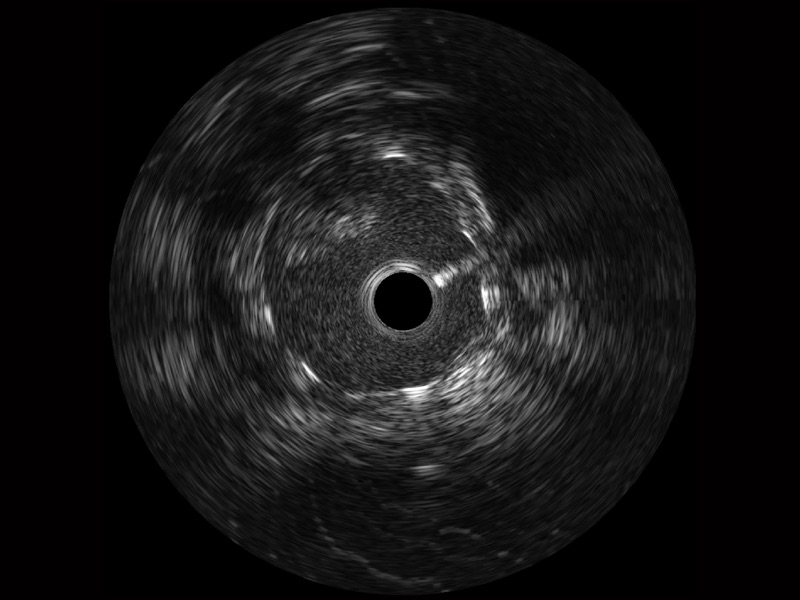

milan米兰宽频IVUS图像

对比传统IVUS导管成像,milan米兰宽频IVUS图像的近场支架梁显影更细腻,远场中膜外血管仍清晰可辨,兼顾远中近,兼顾分辨力与穿透深度